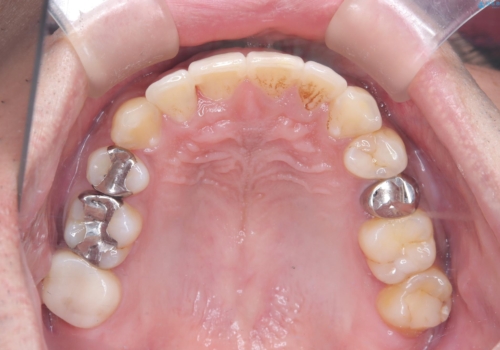

【ワイヤー矯正】八重歯と下の歯の凸凹を治したい

- 主訴:右上の八重歯と、下の歯の凸凹を治したい

上顎右側第一小臼歯と下顎右側第一小臼歯を抜歯しワイヤー矯正を行いました。

右側2級、左側1関係だったため、右側上下第一小臼歯を抜歯し、ワイヤー矯正を行いました。